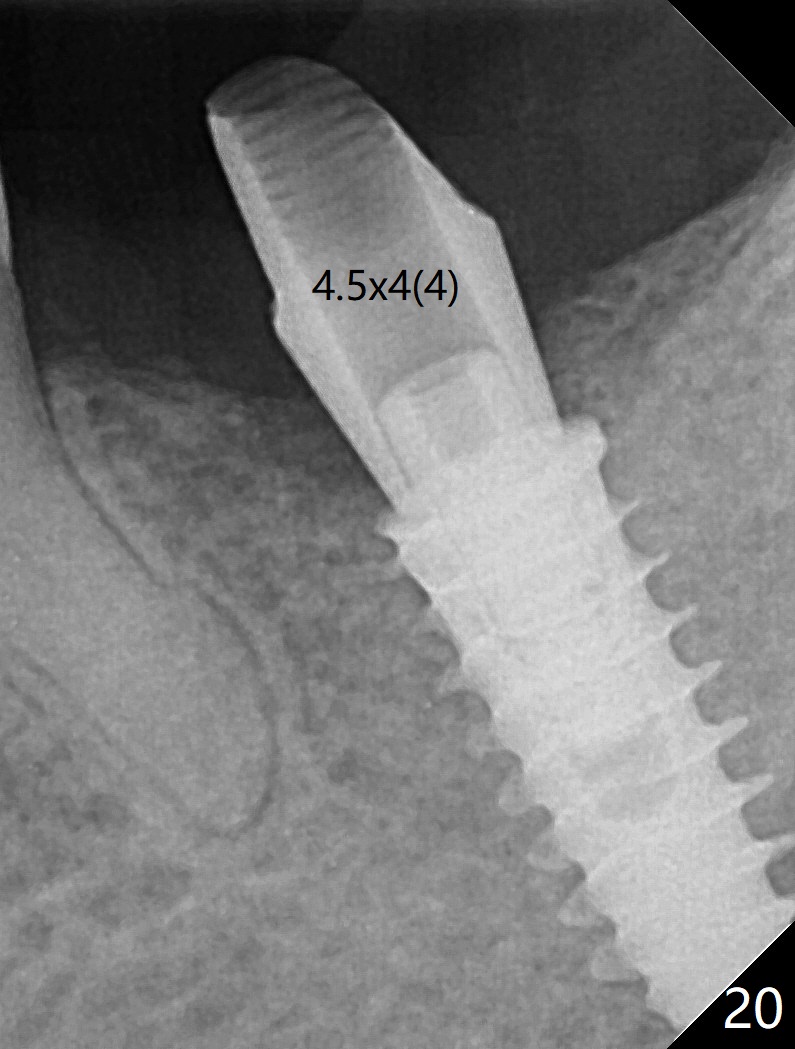

After placement of a 5x11 mm implant and cover screw at #18, allograft mixed with PRF (sticky bone) is placed in the peri-implant space, but it appears that bone density in the apical region (Fig.1 A) is lower than that in the coronal one (C) because of a constriction between the implant and the distal crest (*). Ideally the undercuts (Fig.2 *) of the extraction socket (black area) should be identified. Place bone graft in the undercuts (Fig.3 red circles) after osteotomy (white outlines) and before implant placement! A 4.5x1 mm temporary abutment is placed for an immediate provisional. The 2nd shortcoming of this case is that the implant is placed a little buccal. The papilla mesial to the immediate provisional (Fig.4 P) looks normal 4 days postop (no food impaction is expected when a final restoration is cemented). Additional acrylic (*) was placed to close a buccal gap when the provisional was seated with the temporary abutment. The patient reports loss of a piece of material in 4 days. It must be the additional acrylic, since it is absent 6 weeks postop (Fig.5). The provisional (Fig.5 P) looks wide, probably related to post-extraction gingiva and bone atrophy (Fig.6, 7 *). Bone graft (Fig.6 <) becomes a component of the gingival cuff. The provisional is re-trimmed for better oral hygiene. The gingival cuff is basically healthy 3.5 months postop, although the temporary abutment is loose and the implant is tender to rewinding and winding (Fig.8). The implant seems to remain non-osteointegrated 3.5 months postop (Fig.9). Although the bone density around the implant increases nearly 6 months postop (Fig.10), the implant remains tender when a 5x4(4) mm pair abutment is tightened. The healing abutment is reused. The bone density around the implant increases 11 months postop (Fig.11). Uncover is done with 5.5 mm profile drill. One month post uncover (12 months postop), the implant remains unstable (Fig.12). Prepare sticky bone x1. Make incision for exploration, including retightening the implant after Titanium brush and H2O2 Q-tip rubbing. If needed, a larger and shorter UF implant is a replacement (Fig.13). The implant is removed, cleaned with Titanium brushes and H2O2 in vitro and repositioned 12 months postop (Fig.14: arrow (gaps: post granulation tissue removal)). The gaps are regrafted with sticky bone and covered with PRF membrane and Cytoplast. Although the patient complains of severe pain the first 2-3 postop, the wound is apparently healing 12 days postop. The Cytoplast is exposed asymptomatic 5 weeks postop (Fig.16) and removed (Fig.17). The wound appears to have healed without loss of the bone graft (Fig.18).术后四个月伤口愈合,骨粉几乎没有丢失,有骨小梁形态(图十九:*)。切开,刮匙去骨,有一定硬度,即刻放置修复基台,完全就位(图二十),制备临时牙冠,牙周敷料固定组织瓣(没有缝线)。